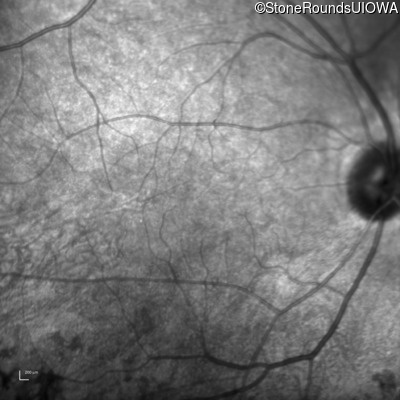

Infrared Fundus Photograph - Right - 20/16

Exemplar